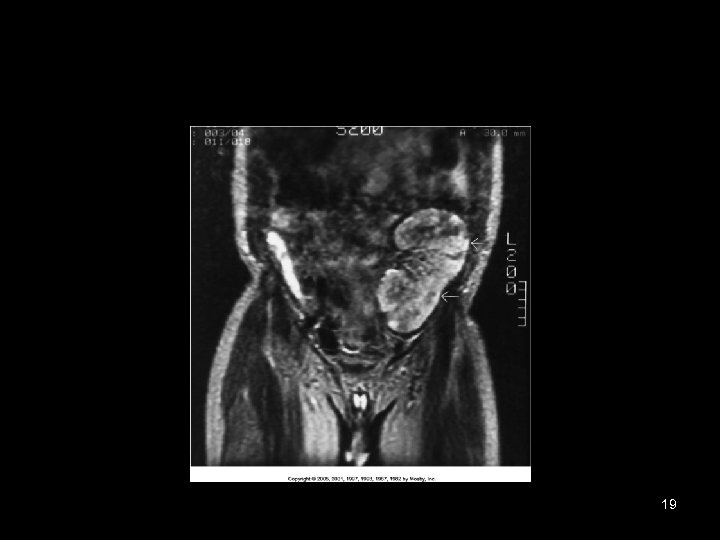

19